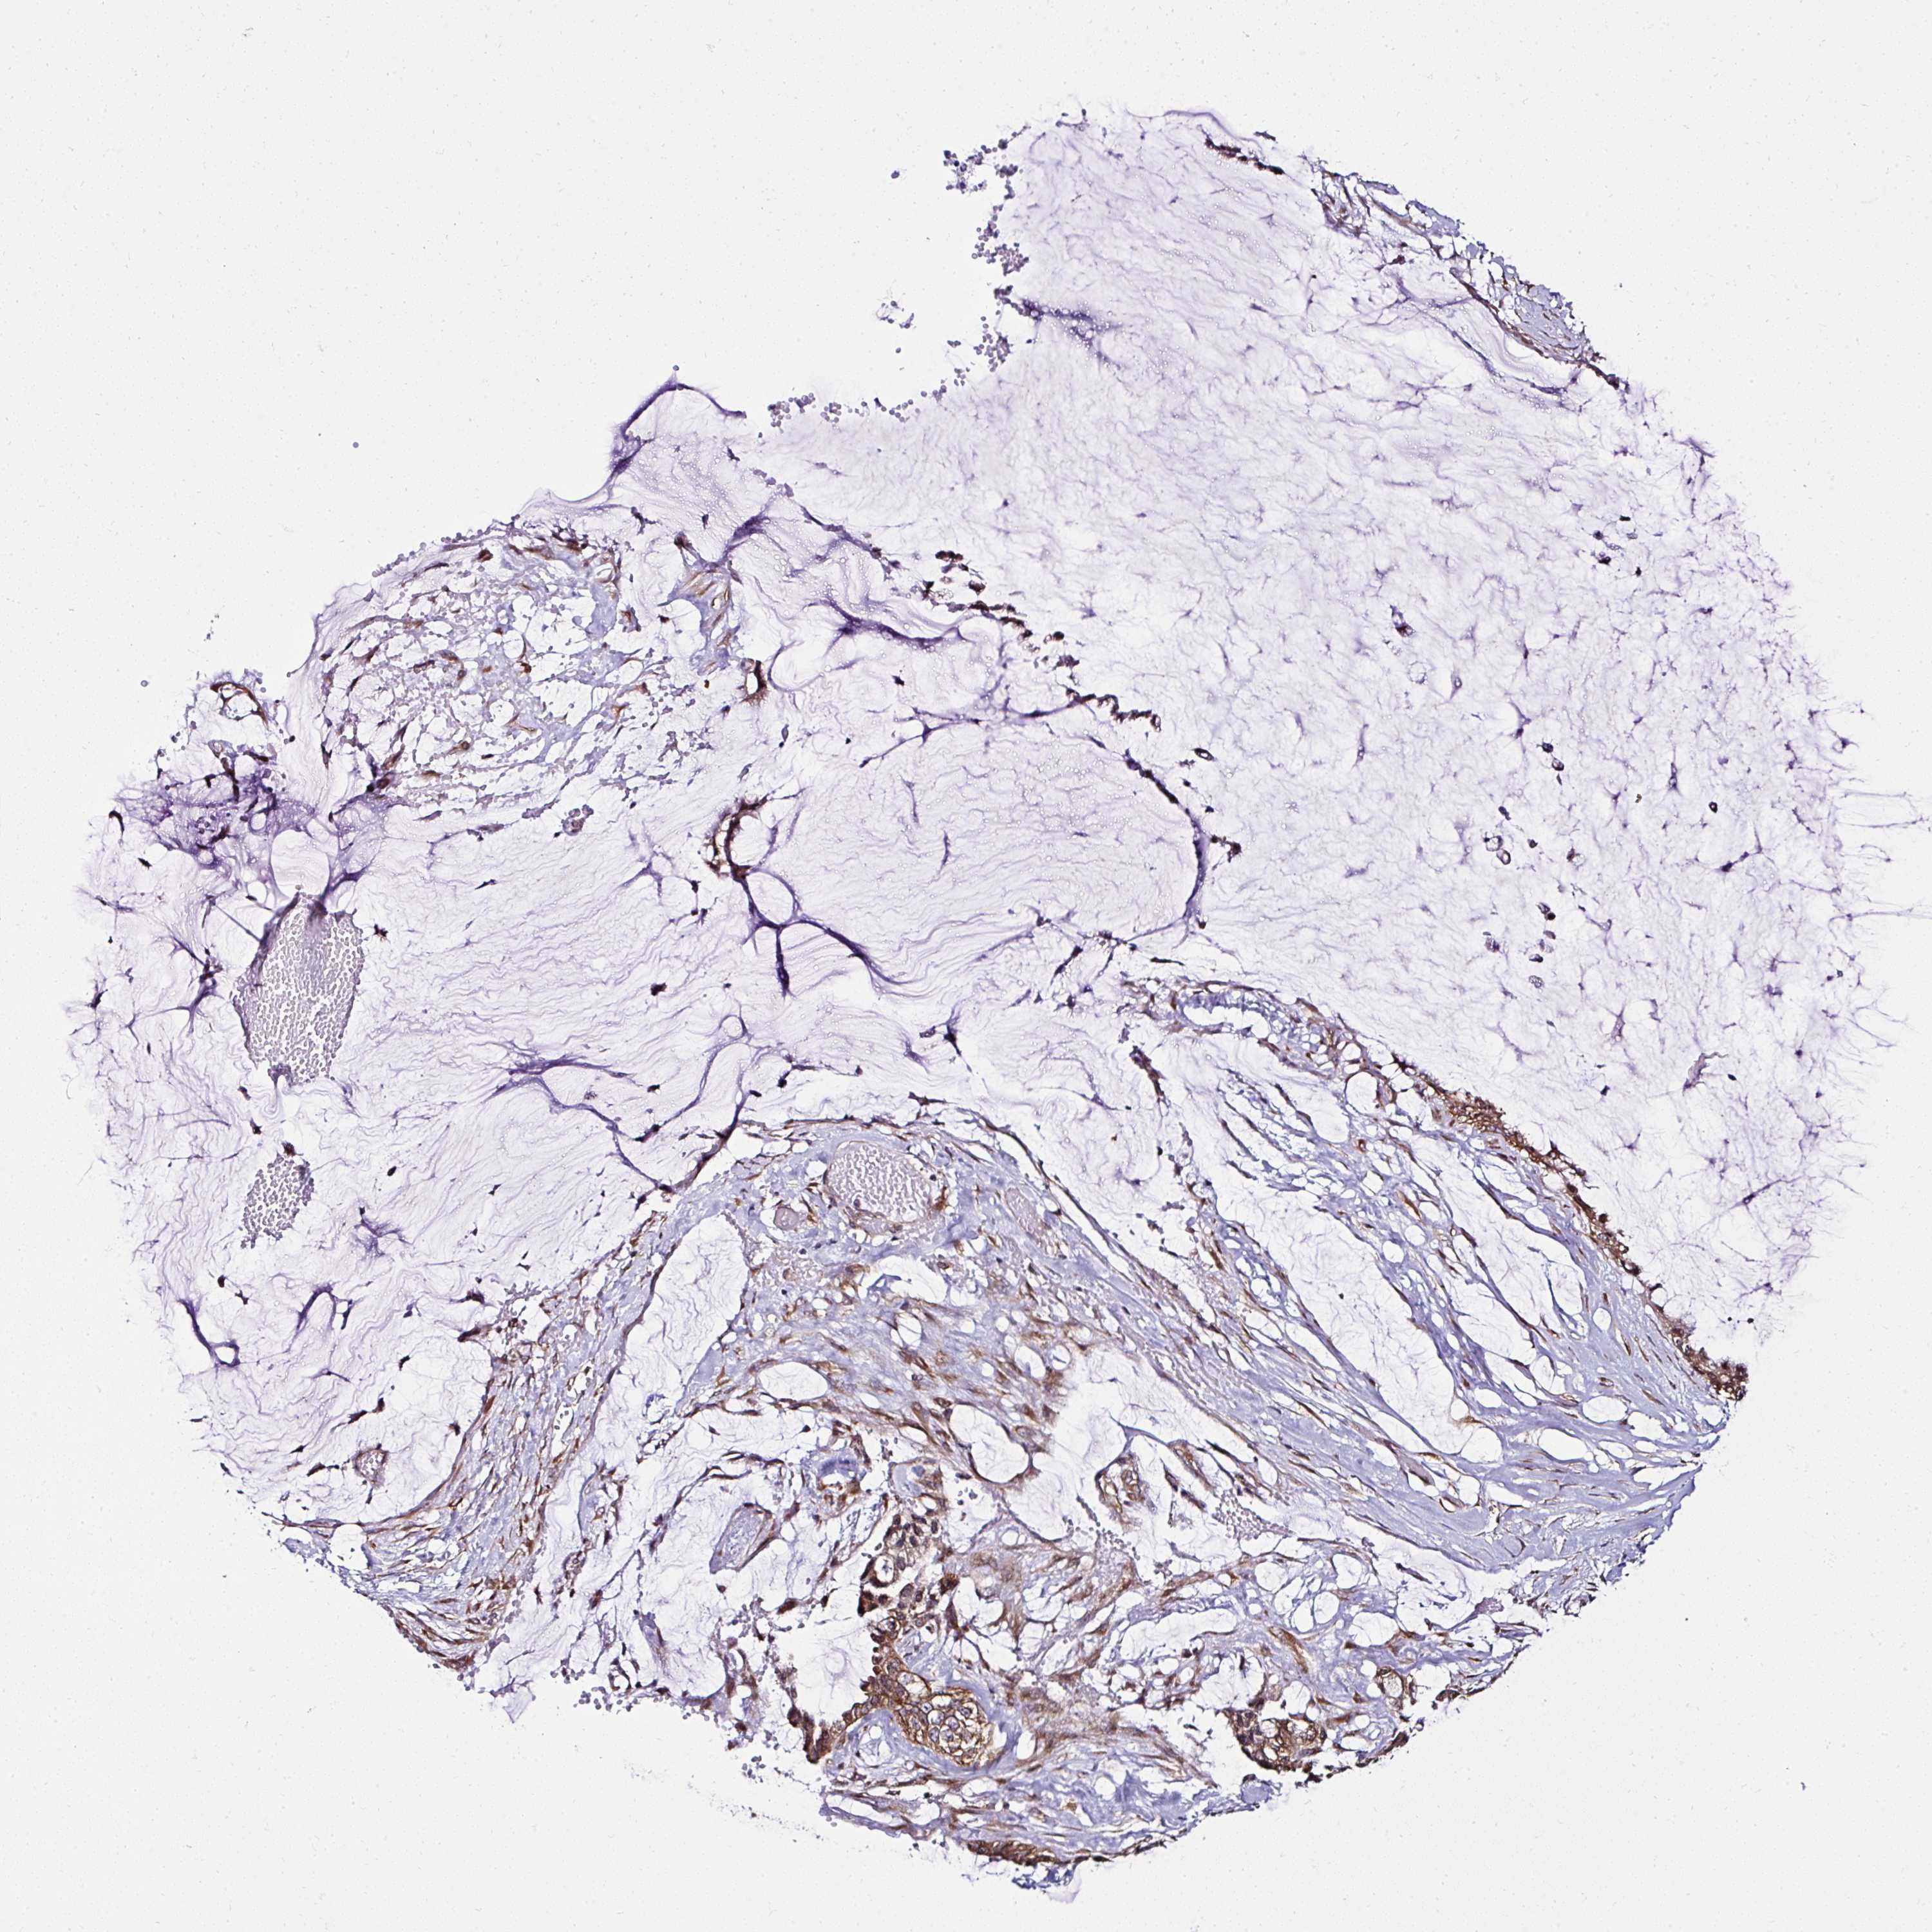

OVARIAN CANCER - Protein expressioni

A mouse-over function shows sample information and annotation data. Click on an image to view it in a full screen mode. Samples can be filtered based on level of antibody staining by selecting one or several of the following categories: high, medium, low and not detected. The assay and annotation is described here.

Note that samples used for immunohistochemistry by the Human Protein Atlas do not correspond to samples in the TCGA dataset.

Antibody stainingi

Antibody staining in the annotated cell types in the current human tissue is reported as not detected, low, medium, or high, based on conventional immunohistochemistry profiling in selected tissues. This score is based on the combination of the staining intensity and fraction of stained cells.

Each image is clickable and will lead to virtual microscopy that enables deeper exploration of all samples and also displays staining intensity scores, fraction scores and subcellular localization as well as patient and tissue information for each sample.

Antibody HPA056586

Staining

High

Medium

Low

Not detected

Intensity

Strong

Moderate

Weak

Negative

Quantity

>75%

75%-25%

<25%

None

Location

Nuclear

Cytoplasmic/membranous

Cytoplasmic/membranous,nuclear

Cystadenocarcinoma, serous, NOS

Carcinoma, endometroid

Cystadenocarcinoma, mucinous, NOS

Carcinoma, NOS